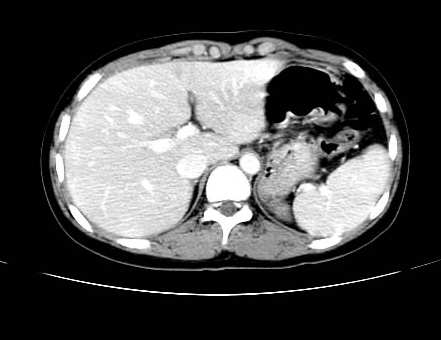

女 16岁  右上腹痛一天,无其他不适

肿块最大径位于十二指肠降段与水平段移行处,并且与肝脏压迹呈“0”形征,可以考虑位于肝外并与胃肠道关系紧密,考虑胃肠道间质瘤(gist)可能较大,须除外神经节起源肿瘤。

肿块与十二指肠关系密切,支持间质瘤诊断.肝脏与结肠均为受压改变.

我坚决反对您的观点,该病例定位:横结肠肝曲与升结肠之间的肠系膜及部分肠壁。请看下图:

病灶巨大,少部分向肠腔内生长,大部分向长腔外生长。其密度不均匀,增强显示明显不均匀强化,并见有大片状始终不强化的不规则坏死液化区。虽然病灶中上部形态尚可,病人又如此年轻,但中下部形态、密度、强化特点强烈提示为恶性病灶。综上,我考虑本病例为:恶性胃肠道间质瘤。